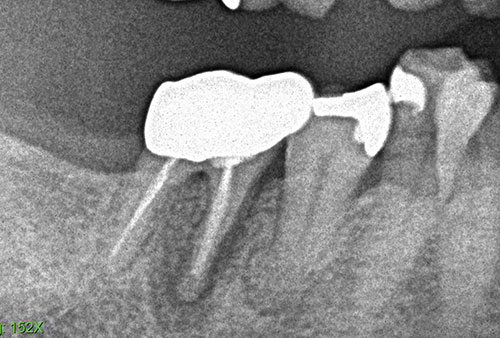

根管治療を行う前に、画像診断で形状を確認します。多くの歯科医院では「2次元」のレントゲンで撮影しますが、レントゲンでは初期の患部を見つけにくい上、根管の複雑な形状をしっかり確認するには力不足です。

そこで、当院では「3次元」で撮影ができる「CT」を利用します。CTはお口の周囲を360度回転しながら撮影するので、レントゲンでは写し出せない患部の様子が詳細にわかります。

日本国内の歯科医院におけるCTの普及率は、5〜10%程度と言われます。

充てん剤が根の先までしっかり入っているか、レントゲンで確認します。隙間ができている場合は、再度薬剤を入れ直し隙間を埋めていきます。

レントゲン撮影で歯の根の先までしっかりと薬剤が入っていることが確認できたら、土台を形成し、被せ物をします。